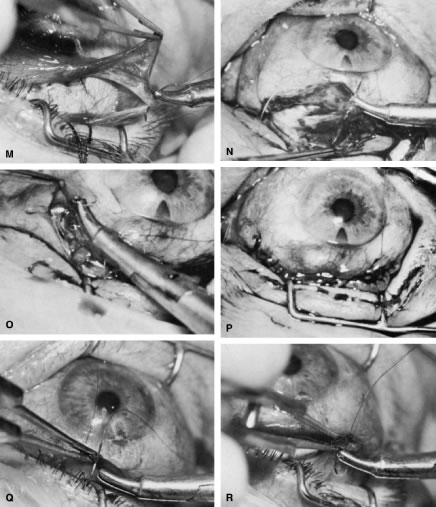

of a limbus-based flap appears unjustifiably difficult and risky.    Fig. 13. Limbus-based flap procedure. A. Conjunctiva is lifted away from the globe, stretched, and incised adjacent

to the superior rectus muscle bridle suture. B. The incision in the conjunctiva is extended nasally. C. The conjunctival incision is extended temporally. D. Tenon's capsule is lifted up, away from the globe, and incised with

the scissors held obliquely to avoid cutting into the underlying superior

rectus muscle. E. The incision in Tenon's capsule is spread bluntly. F. The superior rectus muscle can be seen through the buttonhole in Tenon's

capsule. Bleeding should be minimal; if it occurs, it should be

controlled promptly with cautery. G. Tenon's capsule is incised nasally and temporally. H. The connective tissue overlying the superior rectus muscle is seen easily

after Tenon's capsule has been incised. This tissue usually is

highly vascular in the area directly at the base of the superior rectus

muscle. I. Episclera is buttonholed approximately 4 mm posterior to the limbus, showing

the underlying sclera. J. One blade of the scissors is insinuated between the sclera and the episclera, and

the episclera is incised nasally. K. The episclera is incised temporally. The plane of the scissors is flush

with the sclera. L. Remaining adhesions between the episclera and sclera are dissected in

a semisharp fashion with the no. 67 Beaver blade, which is pushed at right

angles to the cutting axis. M. Tenon's capsule is closed in a separate layer with an 8-0 absorbable

suture. N. The superior edge of Tenon's capsule tends to retract up under the

lid. It can be hooked over the needle and pulled inferiorly. Sutures

are locked. O. After Tenon's capsule is closed, the needle is placed from the underneath

side to the superficial side of the conjunctiva and exteriorized

so that it can be used to close the conjunctiva. P. The conjunctiva is closed with closely spaced running, unlocked sutures. The

final suture is tied securely. Q. After the needle has passed through the tissue, it is lifted away from

the globe firmly. The underlying tissue is stretched. A blunt forceps

is used to grasp this underlying tissue firmly, as close to the needle

as possible. This maneuver will hold the needle firmly in place, permitting

the surgeon to release the end of the needle containing the suture

without having to change the position of the needle. R. The needle can be regrasped toward the cutting end so that it is held

in proper position for placement of the next suture. (Spaeth GL. Glaucoma surgery. In Spaeth GL (ed). Ophthalmic Surgery: Principles

and Practice. Philadelphia: WB Saunders, 1990.) Fig. 13. Limbus-based flap procedure. A. Conjunctiva is lifted away from the globe, stretched, and incised adjacent

to the superior rectus muscle bridle suture. B. The incision in the conjunctiva is extended nasally. C. The conjunctival incision is extended temporally. D. Tenon's capsule is lifted up, away from the globe, and incised with

the scissors held obliquely to avoid cutting into the underlying superior

rectus muscle. E. The incision in Tenon's capsule is spread bluntly. F. The superior rectus muscle can be seen through the buttonhole in Tenon's

capsule. Bleeding should be minimal; if it occurs, it should be

controlled promptly with cautery. G. Tenon's capsule is incised nasally and temporally. H. The connective tissue overlying the superior rectus muscle is seen easily

after Tenon's capsule has been incised. This tissue usually is

highly vascular in the area directly at the base of the superior rectus

muscle. I. Episclera is buttonholed approximately 4 mm posterior to the limbus, showing

the underlying sclera. J. One blade of the scissors is insinuated between the sclera and the episclera, and

the episclera is incised nasally. K. The episclera is incised temporally. The plane of the scissors is flush

with the sclera. L. Remaining adhesions between the episclera and sclera are dissected in

a semisharp fashion with the no. 67 Beaver blade, which is pushed at right

angles to the cutting axis. M. Tenon's capsule is closed in a separate layer with an 8-0 absorbable

suture. N. The superior edge of Tenon's capsule tends to retract up under the

lid. It can be hooked over the needle and pulled inferiorly. Sutures

are locked. O. After Tenon's capsule is closed, the needle is placed from the underneath

side to the superficial side of the conjunctiva and exteriorized

so that it can be used to close the conjunctiva. P. The conjunctiva is closed with closely spaced running, unlocked sutures. The

final suture is tied securely. Q. After the needle has passed through the tissue, it is lifted away from

the globe firmly. The underlying tissue is stretched. A blunt forceps

is used to grasp this underlying tissue firmly, as close to the needle

as possible. This maneuver will hold the needle firmly in place, permitting

the surgeon to release the end of the needle containing the suture

without having to change the position of the needle. R. The needle can be regrasped toward the cutting end so that it is held

in proper position for placement of the next suture. (Spaeth GL. Glaucoma surgery. In Spaeth GL (ed). Ophthalmic Surgery: Principles

and Practice. Philadelphia: WB Saunders, 1990.)